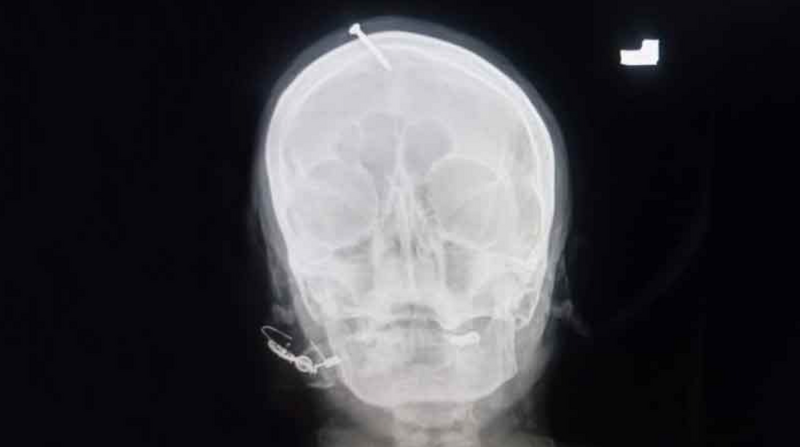

ڈاکٹر سلیمان نے بتایا کہ خاتون کو چند روز قبل اسپتال لایا گیا تھا،ان کے سر سے خون بہہ رہا تھا۔

In a shocking incident in Peshawar, a self-proclaimed faith healer - ‘Pir,’ hammered a nail into a pregnant...